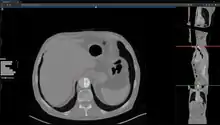

Studierfenster[1][2] is a free, non-commercial Open Science client/server-based Medical Imaging Processing (MIP) online framework. It offers capabilities, like viewing medical data (Computed Tomography (CT), Magnetic Resonance Imaging (MRI), etc.) in two-dimensional (2D) and three-dimensional space (3D) directly in a standard web browser, like Google Chrome, Mozilla Firefox, Safari or Microsoft Edge. Other functionalities are the calculation of Medical Metrics (Dice Score[3] and Hausdorff distance[4]), manual slice-by-slice outlining of structures in medical images (segmentation[5][6]), manual placing of (anatomical) landmarks in medical image data, viewing medical data in Virtual Reality (VR) and a facial reconstruction and registration of medical data for Augmented Reality (AR).[7]

Other features of Studierfenster are the automatic Cranial Implant Design with a neural network,[8][9] the inpainting of Aortic Dissections[10] with a Generative Adversarial Network(GAN)[11][12] and an automatic aortic landmark detection with Deep Learning[13] in Computed Tomography Angiography (CTA) scans.

Features